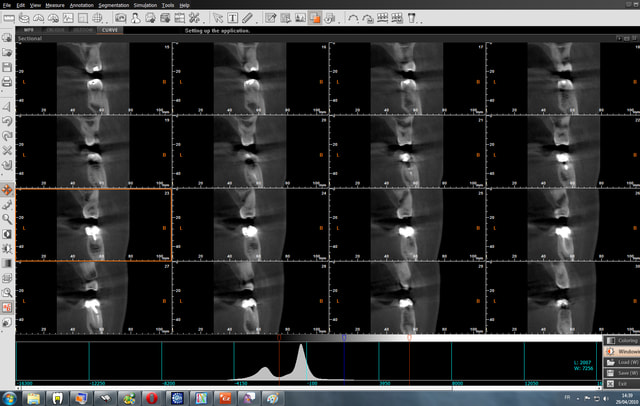

30/04/2010 à 00h49

Bon finalement j'ai fait mon choix, cone beam installé hier !

Vatech Ewoo.

Pour moi les plus :

- taille de champ variable: 5*5 8*5 8*8 12.5*8

- vraie combo pano/cone beam

- interface sympa

- artefact métallique limité

- Logiciel d'imagerie et planification implantaire très bien

(pour info c'est une version d'Ondemand3D à l'essaie pour 90j ici:

http://www.ondemand3d.com/Content/Download/Trial.aspx prix du soft environ 5000$)

- budget compétitif

quelques clichés d'essais